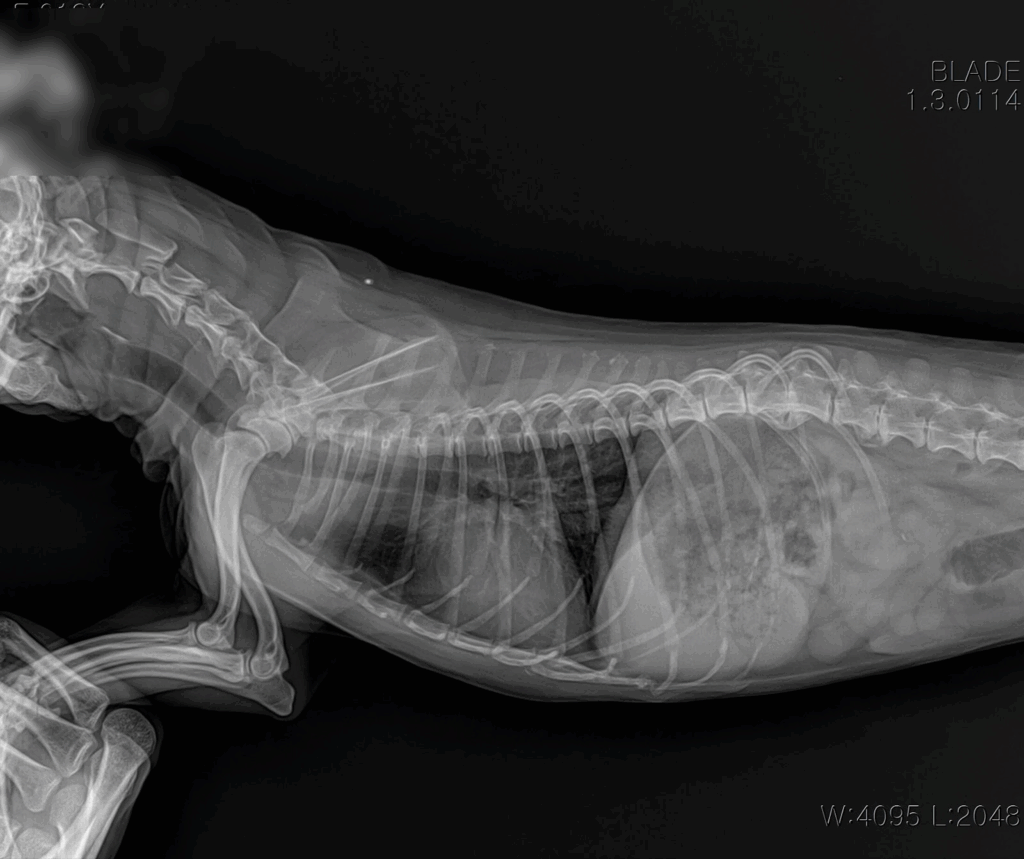

📌 흉부 X-ray

X-ray 촬영은 심장의 크기와 모양, 그리고 폐에 물이 차 있는지 여부를 확인하는 데 사용됩니다. 이를 통해 심장비대나 폐수종 같은 합병증 여부를 빠르게 파악할 수 있습니다.

내원 즉시, 적극적인 산소처치와 안정화가 먼저 이루어졌습니다. 호흡곤란 환자는 응급 상황으로 진행될 수 있기 때문에, 빠른 산소 공급과 안정을 통해 위험을 줄이는 것이 최우선입니다. 이후 상태가 안정되자 심장 초음파와 흉부 방사선을 통한 정밀 진단이 진행되었습니다.

내원 당시 흉부 방사선 사진: 심장 비대 및 폐수종 확인